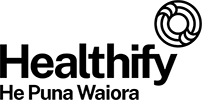

Respiratory diseases

Respiratory diseases are conditions that affect any of the processes involved with breathing. If you or someone you know are one of the 1 in 6 New Zealanders that lives with a respiratory condition, here you can find some useful information on how to manage the condition well.